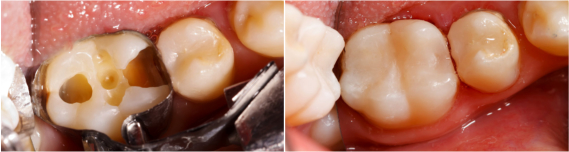

Composite fillings – also known as tooth-colored fillings – are dental restorations designed to be inconspicuous and natural in appearance. They blend well with the teeth and appear more natural than amalgam fillings, which are darker and more easily seen by other people. Composite fillings are made of ceramic and plastic compounds that chemically bond to the teeth. They can be used to fill in decayed areas of the teeth, as well as to help repair chipped or broken teeth. Most dentists use composite restorations to treat the teeth closest to the front of the mouth, as they are more noticeable when patients smile. However, advancements in dental technology and the composition of composite fillings have made it possible for Auburn dentists to also use tooth-colored fillings on molars, which receive more wear than other teeth.

During your visit, your gums and teeth will be anesthetized with a local anesthetic near the site of the filling. Once the area is numb, the decayed or damaged portion of your teeth will be removed to make room for the new tooth-colored filling. A resin will be placed over the area and cured with a hand-held light for less than a minute. The new filling will then be shaped and polished before the procedure is complete.